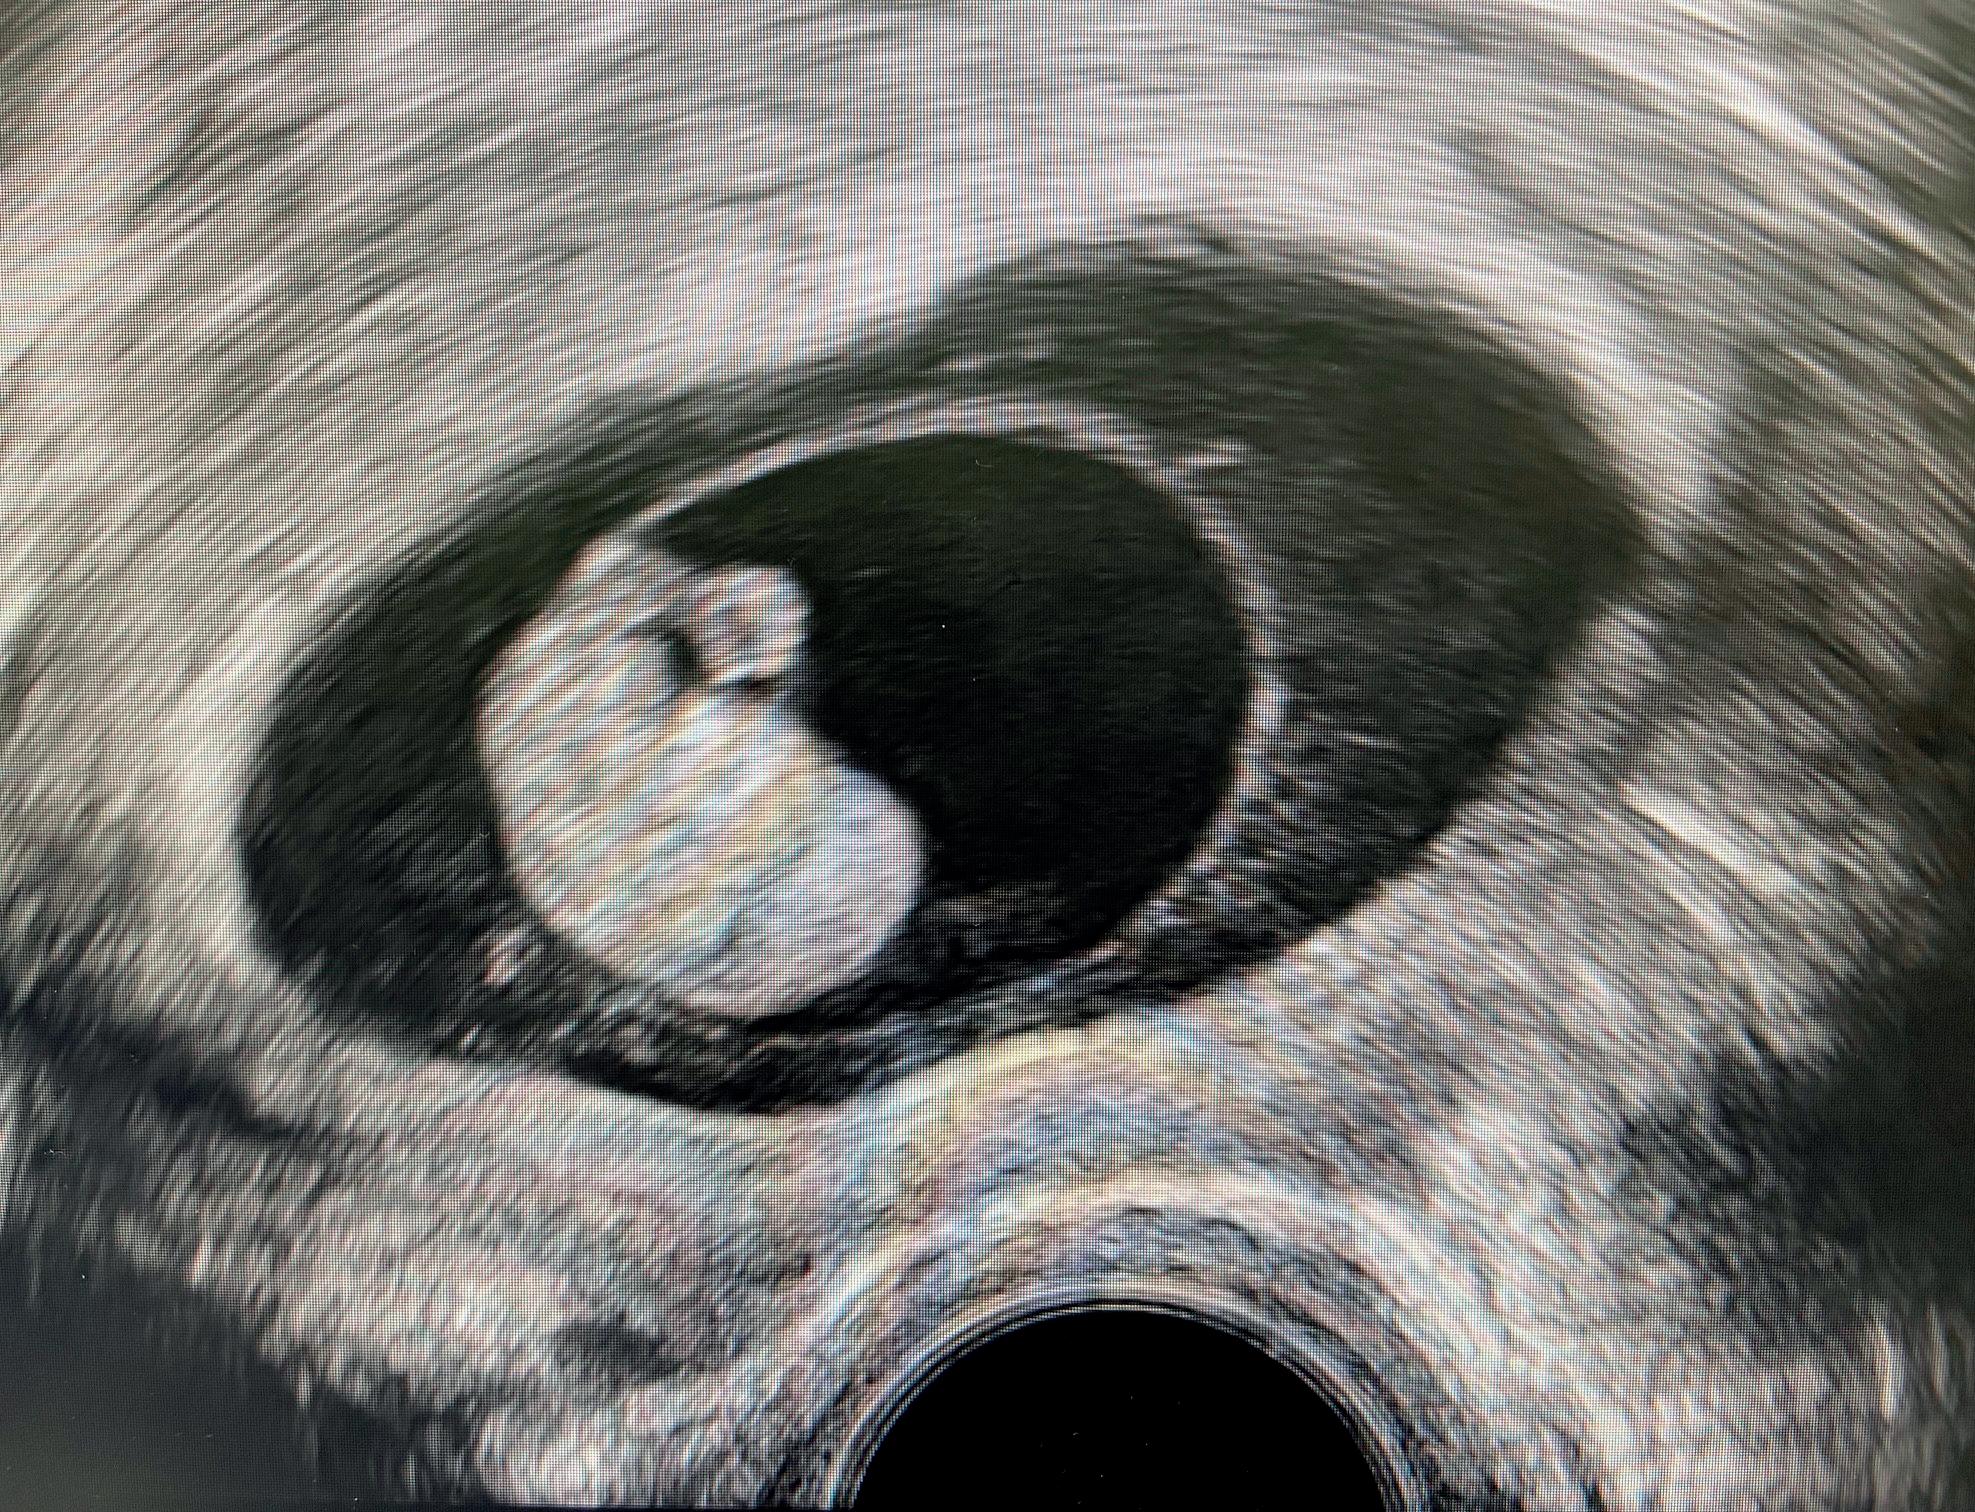

Så kom A-ha-opplevelsene, jeg husker ikke hva min første var, fordi det ble så mange. Kanskje det var å oppdage en veldig tidlig intrauterin graviditet og være trygg på det. Nei, ikke en gestasjonssekk på en centimeter, men bare på noen millimeter. Eller å finne den tubargraviditeten på tre millimeter i pasientens høyre tube. Ser man dem så tidlig, forstår man at svært mange ikke trenger operasjon, men kan behandles med ekspektans. Jeg begynte å forstå arrgraviditeter. Det tok meg hele året, og jeg tror ikke at jeg egentlig hadde noe begrep om det før. Det var gøy å være med å se veldig sjeldne ektopiske graviditeter og hvordan de ble håndtert.

Kurset dekket et bredt spekter av temaer innenfor tidlig svangerskap. Et foredrag som ble veldig godt mottatt var Jackie Ross foredrag om identifisering av tubare ektopiske svangerskap med ultralyd. Flere videoer viste oss nøyaktig hvordan man følger tubene fra interstitium frem til fimbria, både når tubene inneholder et svangerskap og for normale tuber. Dr. Ross viste også eksempler på hvordan endometrium kan se ut ved ektopiske svangerskap, samt tips for å finne et tubart svangerskap.